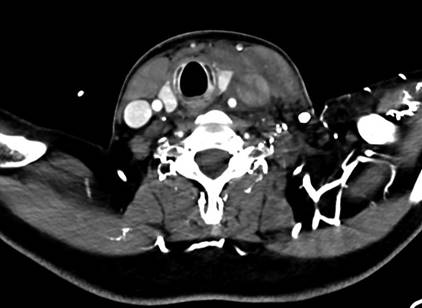

respiratoria mecánica y se administran prostaglandinas. El ecocardiograma Doppler color muestra estenosis aórtica crítica con

disfunción grave del ventrículo izquierdo (Figura 1A).

Fig. 1. Ecocardiograma Doppler

en donde se observa estenosis aórtica crítica (A). Angiografía desde acceso

carotideo post valvuloplastia aórtica (B).

Reconstrucción angiográfica de cerclaje quirúrgico de

ambas ramas pulmonares (C).

A las 18 horas de vida, se realiza

cateterismo cardíaco combinado y valvuloplastia

aórtica con balón híbrido (Tylsihak Mini, 6.0 ª 20

mm), mediante un acceso carotídeo derecho (disección)

(Figura 1B). Al cuarto día un ecocardiograma evidencia

gradiente transaórtico pico de 16 mmHg

con insuficiencia aórtica leve y comunicación interauricular amplia y ductus permeable.